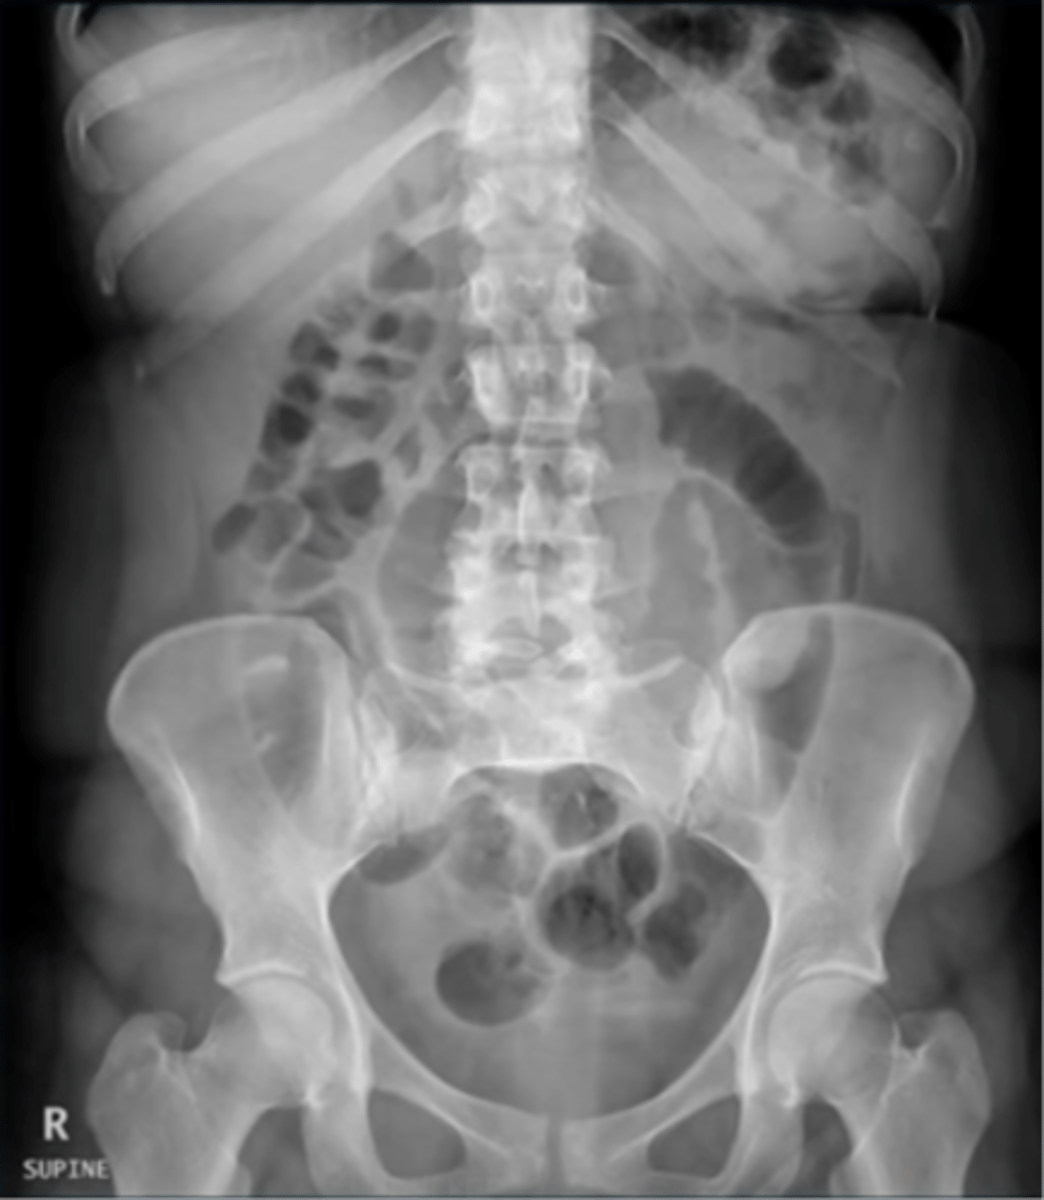

Normal supine AXR